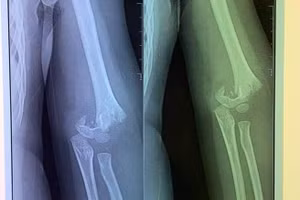

Sở GD&ĐT Hà Nội yêu cầu xác minh vụ trẻ mầm non bị gãy tay 27/09/2020 10:16 GD&TĐ - Liên quan đến việc trẻ bị ngã gãy tay trong Trường mầm non Vườn trẻ thơ (quận Hai Bà Trưng), Sở GD&ĐT Hà Nội đã có văn bản yêu cầu Phòng GD&ĐT và nhà trường xác minh, làm rõ.